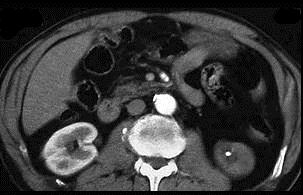

问题 男,48岁,主诉尿色“发红”1周。 运动后血尿,伴左肾区胀痛,诊断可能是 ( )

选项 A、左肾肿瘤 B、左肾结核 C、左肾结石 D、左输尿管结石 E、多囊肾

答案 C